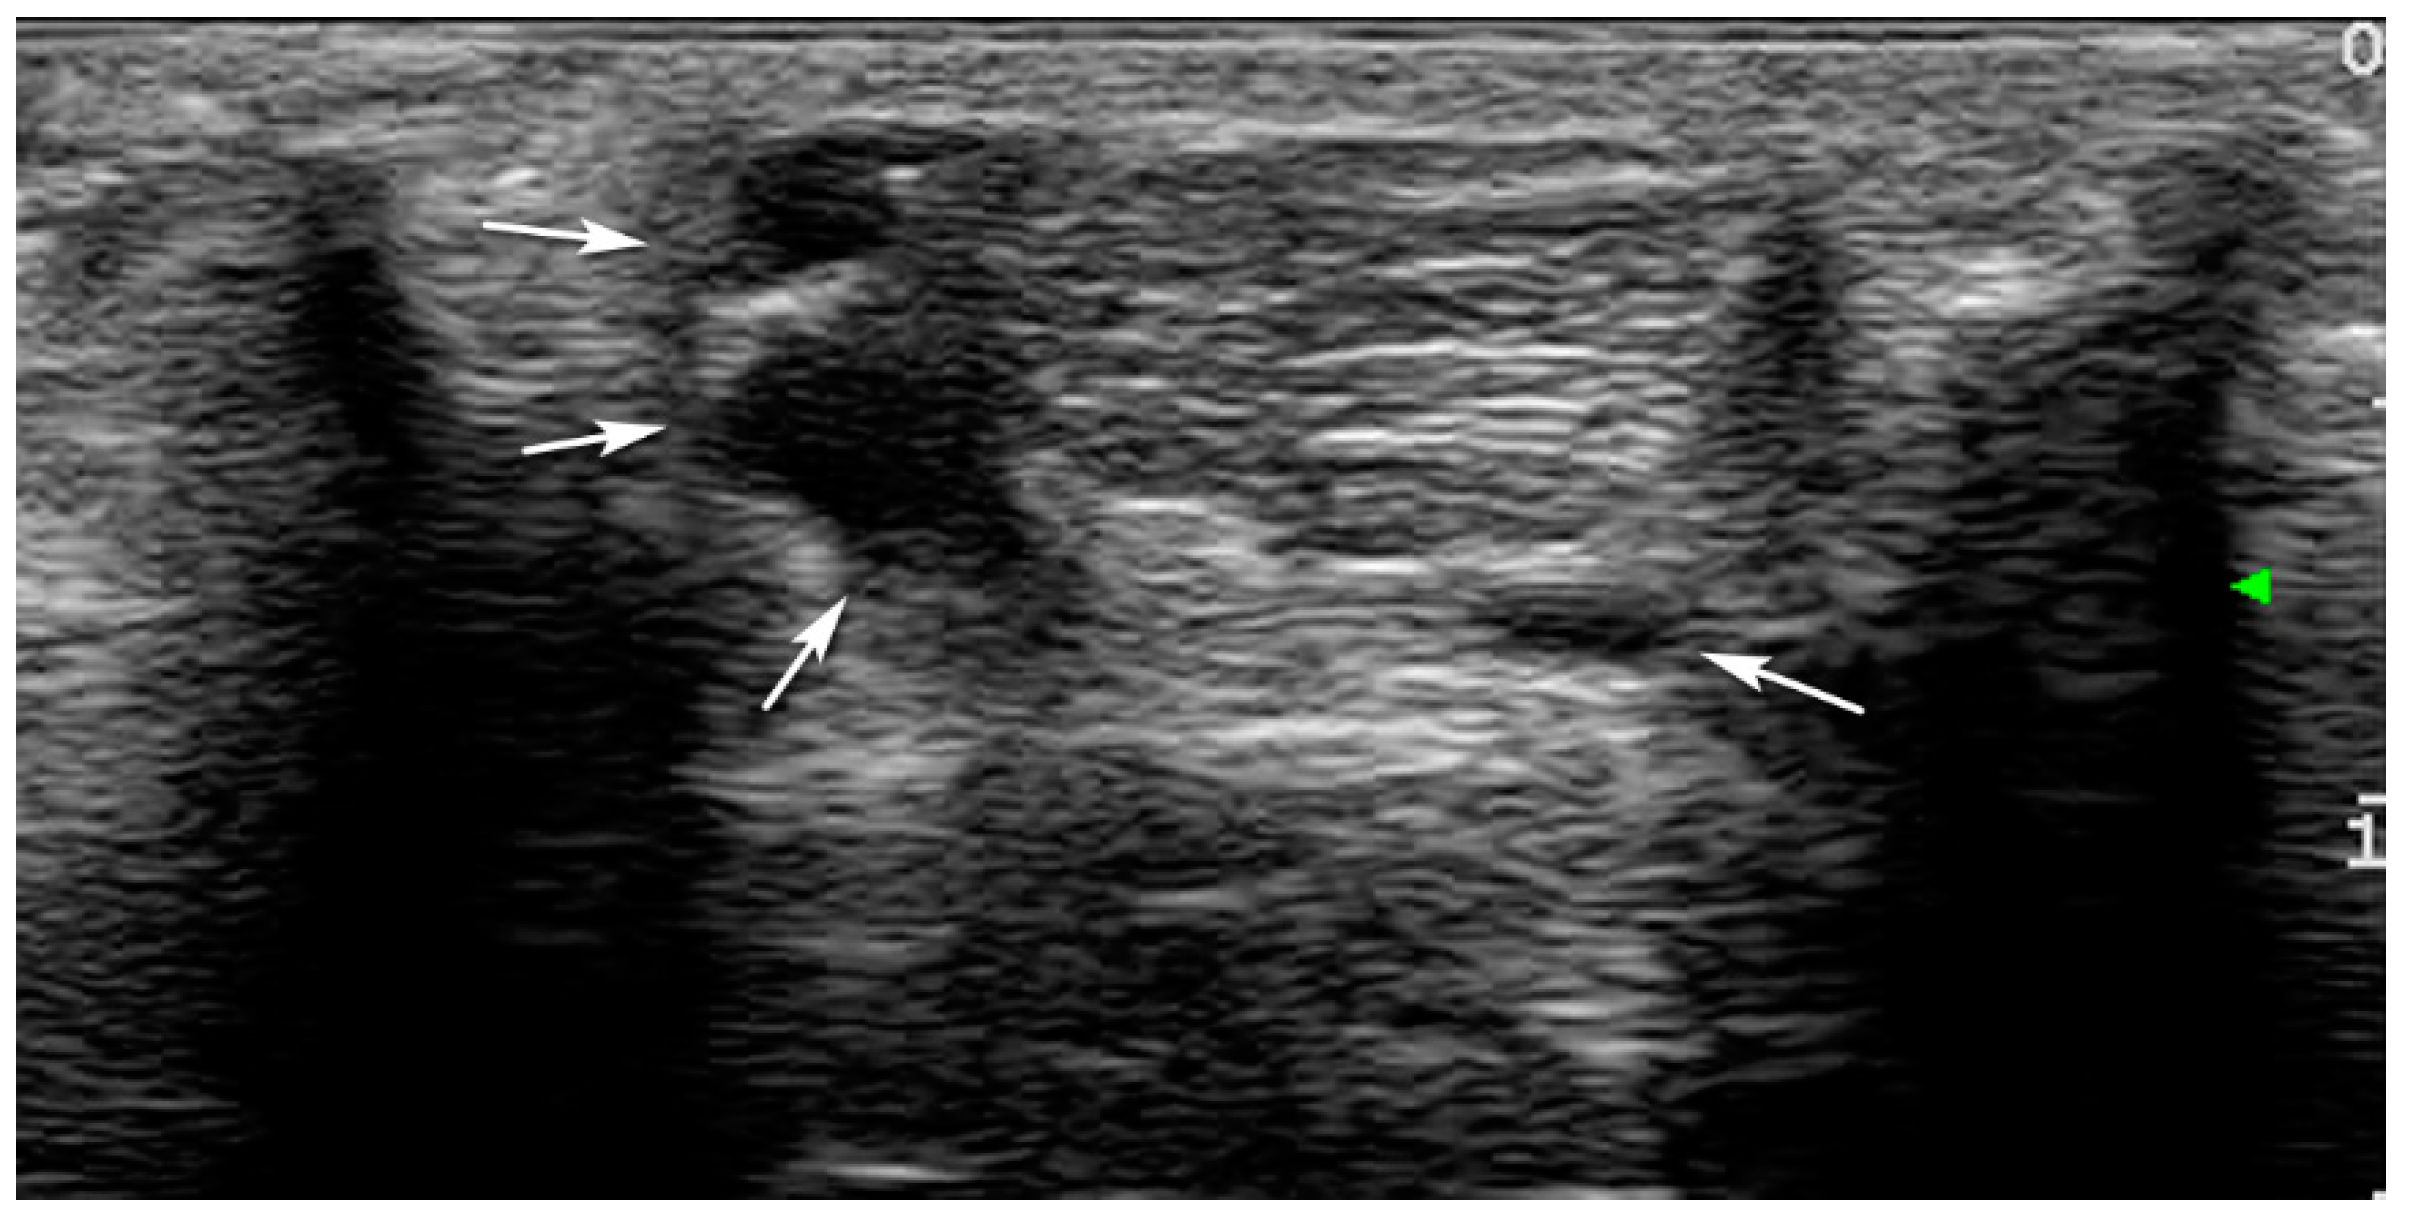

3. Results